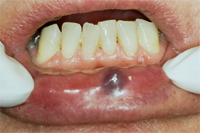

Laser-Zahnmedizin: Fall 4, Hämangiom-Entfernung

Die untere Bildserie beschreibt die Entfernung eines Hämangioms auf der Unterlippe eines 72 Jahre alten Patienten. Ein Hämangiom (Blutschwämmchen) ist ein embryonaler Tumor mit Endothelproliferation und sekundärer Ausbildung von Gefässlumen. Ein Herausschneiden war bei der gegebenen Grösse notwendig. Durch das Alter des Patienten und durch die empfindliche Lokalität des Hämangioms an der Lippe ist ein minimalinvasiver Eingriff mit schneller Wundheilung essentiell. Dies wird durch eine Laserbehandlung garantiert (Abb. 1-6).

Das herausgeschnittene Hämangiom wurde zwecks Untersuchung auf Malignität (bösartiger Tumor) ans Pathologische Institut der Uni Zürich geschickt. Es konnte als gutartig eingestuft werden.